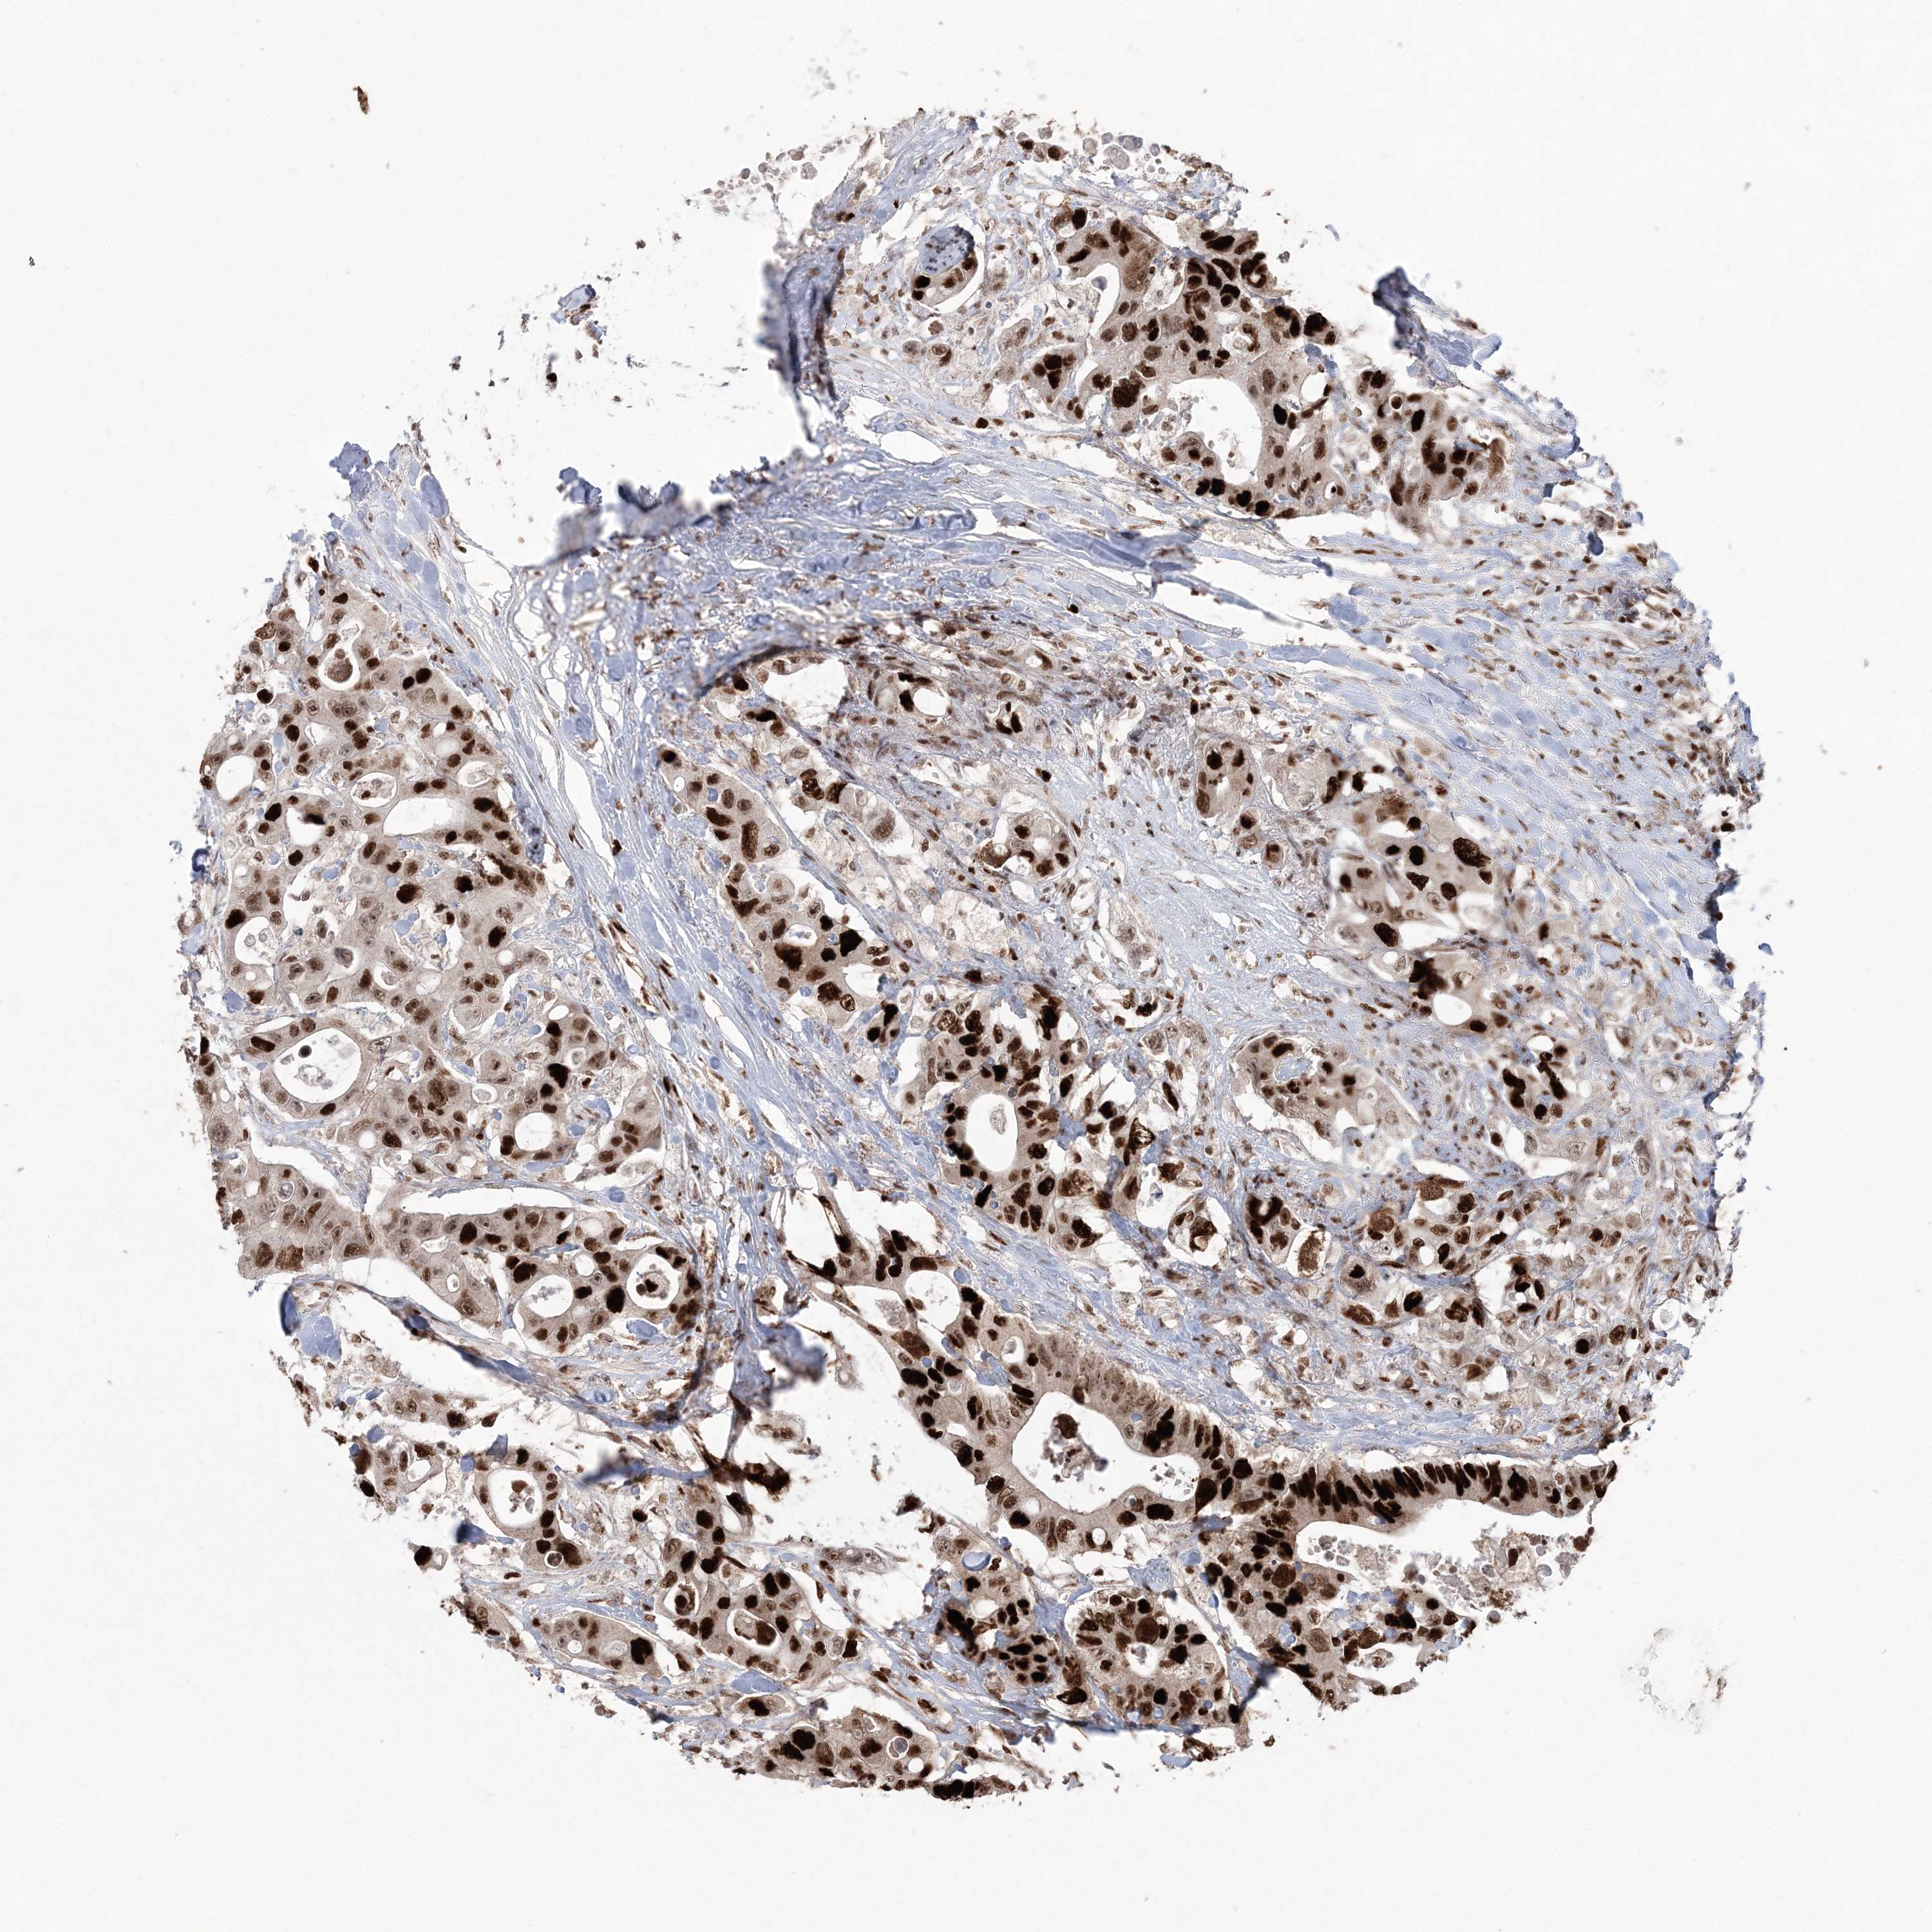

CANCER COLORECTAL CANCER Show tissue menu

ANTIBODIES

AND

VALIDATION

Colorectal cancer

Human cancer

Colon adenocarcinoma